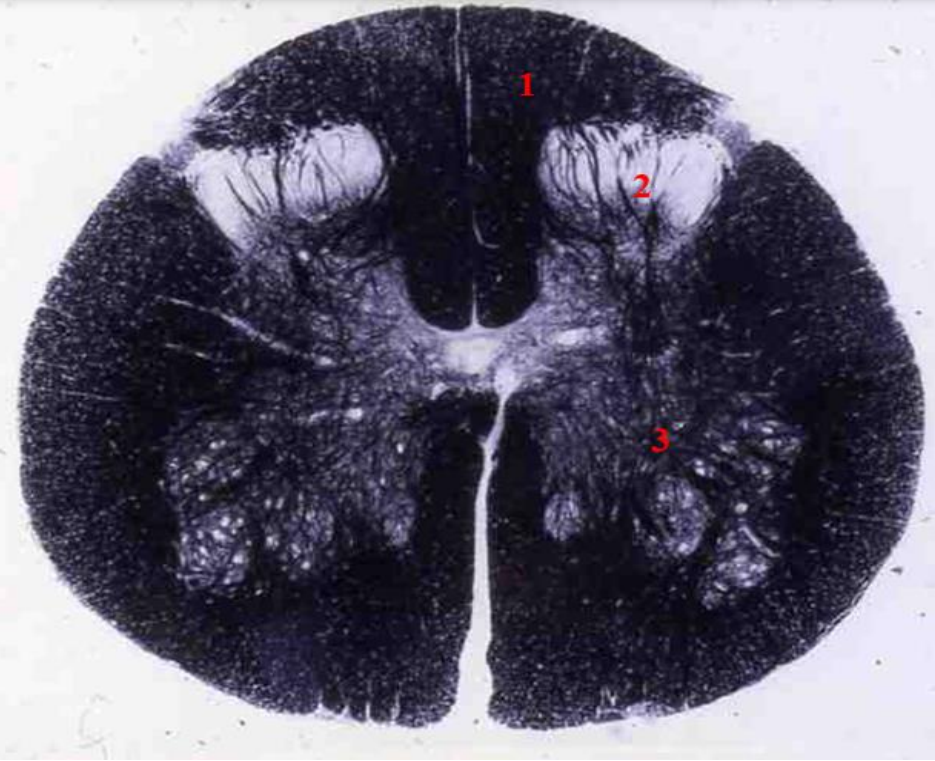

lumbar cord

- fibre tracts are few

- large anterior and posterior horns due to lumbar plexus

1

fasciculus gracilis

2

Q

3

anterior horn